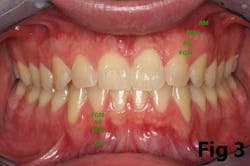

There is an abundance of literature showing increased gingival inflammation around natural dentition (exacerbated when a fixed restoration is present) when there is less than 2 mm AG. (Figs. 8, 9: post grafting) There is an abundance of literature showing increased incidence of peri-implant mucositis when there is inadequate attached tissue — a weaker connective tissue adhesion and lack of Sharpey’s fibers make the peri-implant tissue even more susceptible to bacterial challenge. (1-6, 8, 10) And as periodontitis is always preceded by gingivitis, peri-implantitis will be preceded by peri-implant mucositis. If we can decrease the incidence of peri-implant mucositis by providing a better and more resilient tissue phenotype, we can lower the incidence of peri-implantitis.The FGG procedure is indicated in cases of implant therapy where this is less than 2 mm of attached tissue present. Sometimes, a FGG is preferred over CTG because: (1) the FGG results in greater gain of attached tissue, (2) the FGG alleviates frenum/muscular pull whereas the connective tissue may increase muscular tension after the flap is coronally advanced, and (3) creeping attachment is often a positive byproduct of the FGG procedure.